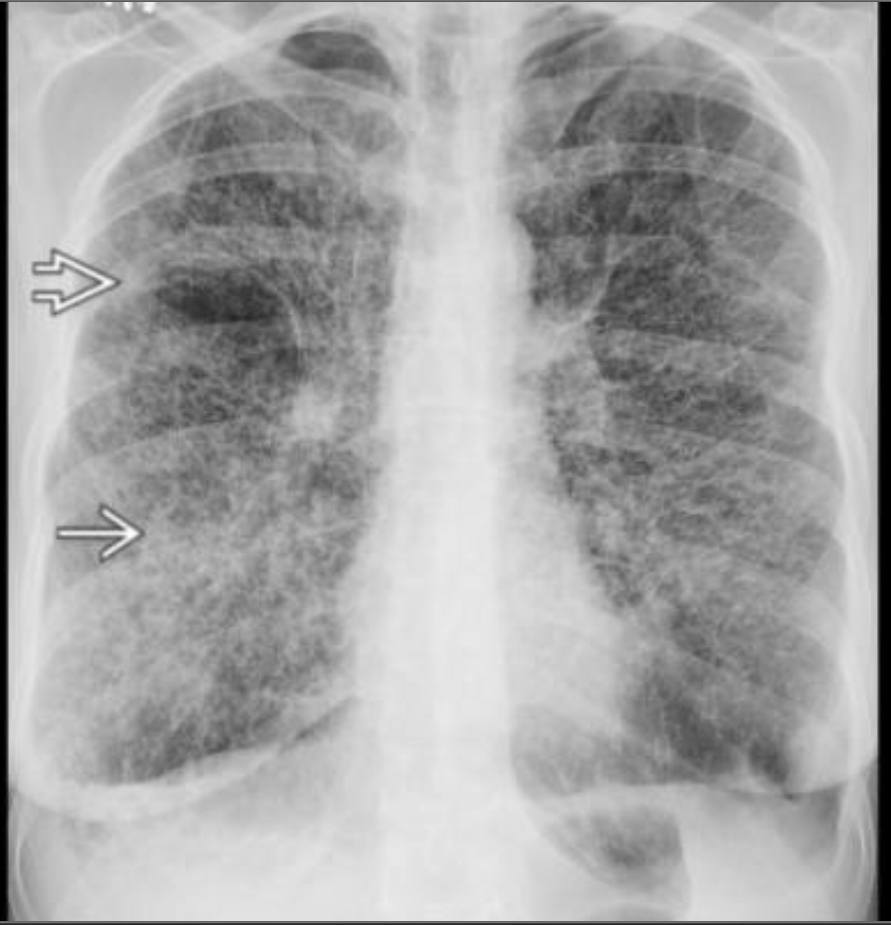

chronic hypersensitivity pneumonitis

Mosaic pattern with areas of ground-glass atenuation and areas of low attenuation.

Fibrosis and parenchymal distortion in a mid zone distribution.

left vs right?

Left UIP w honeycombing

Right Chronic HP